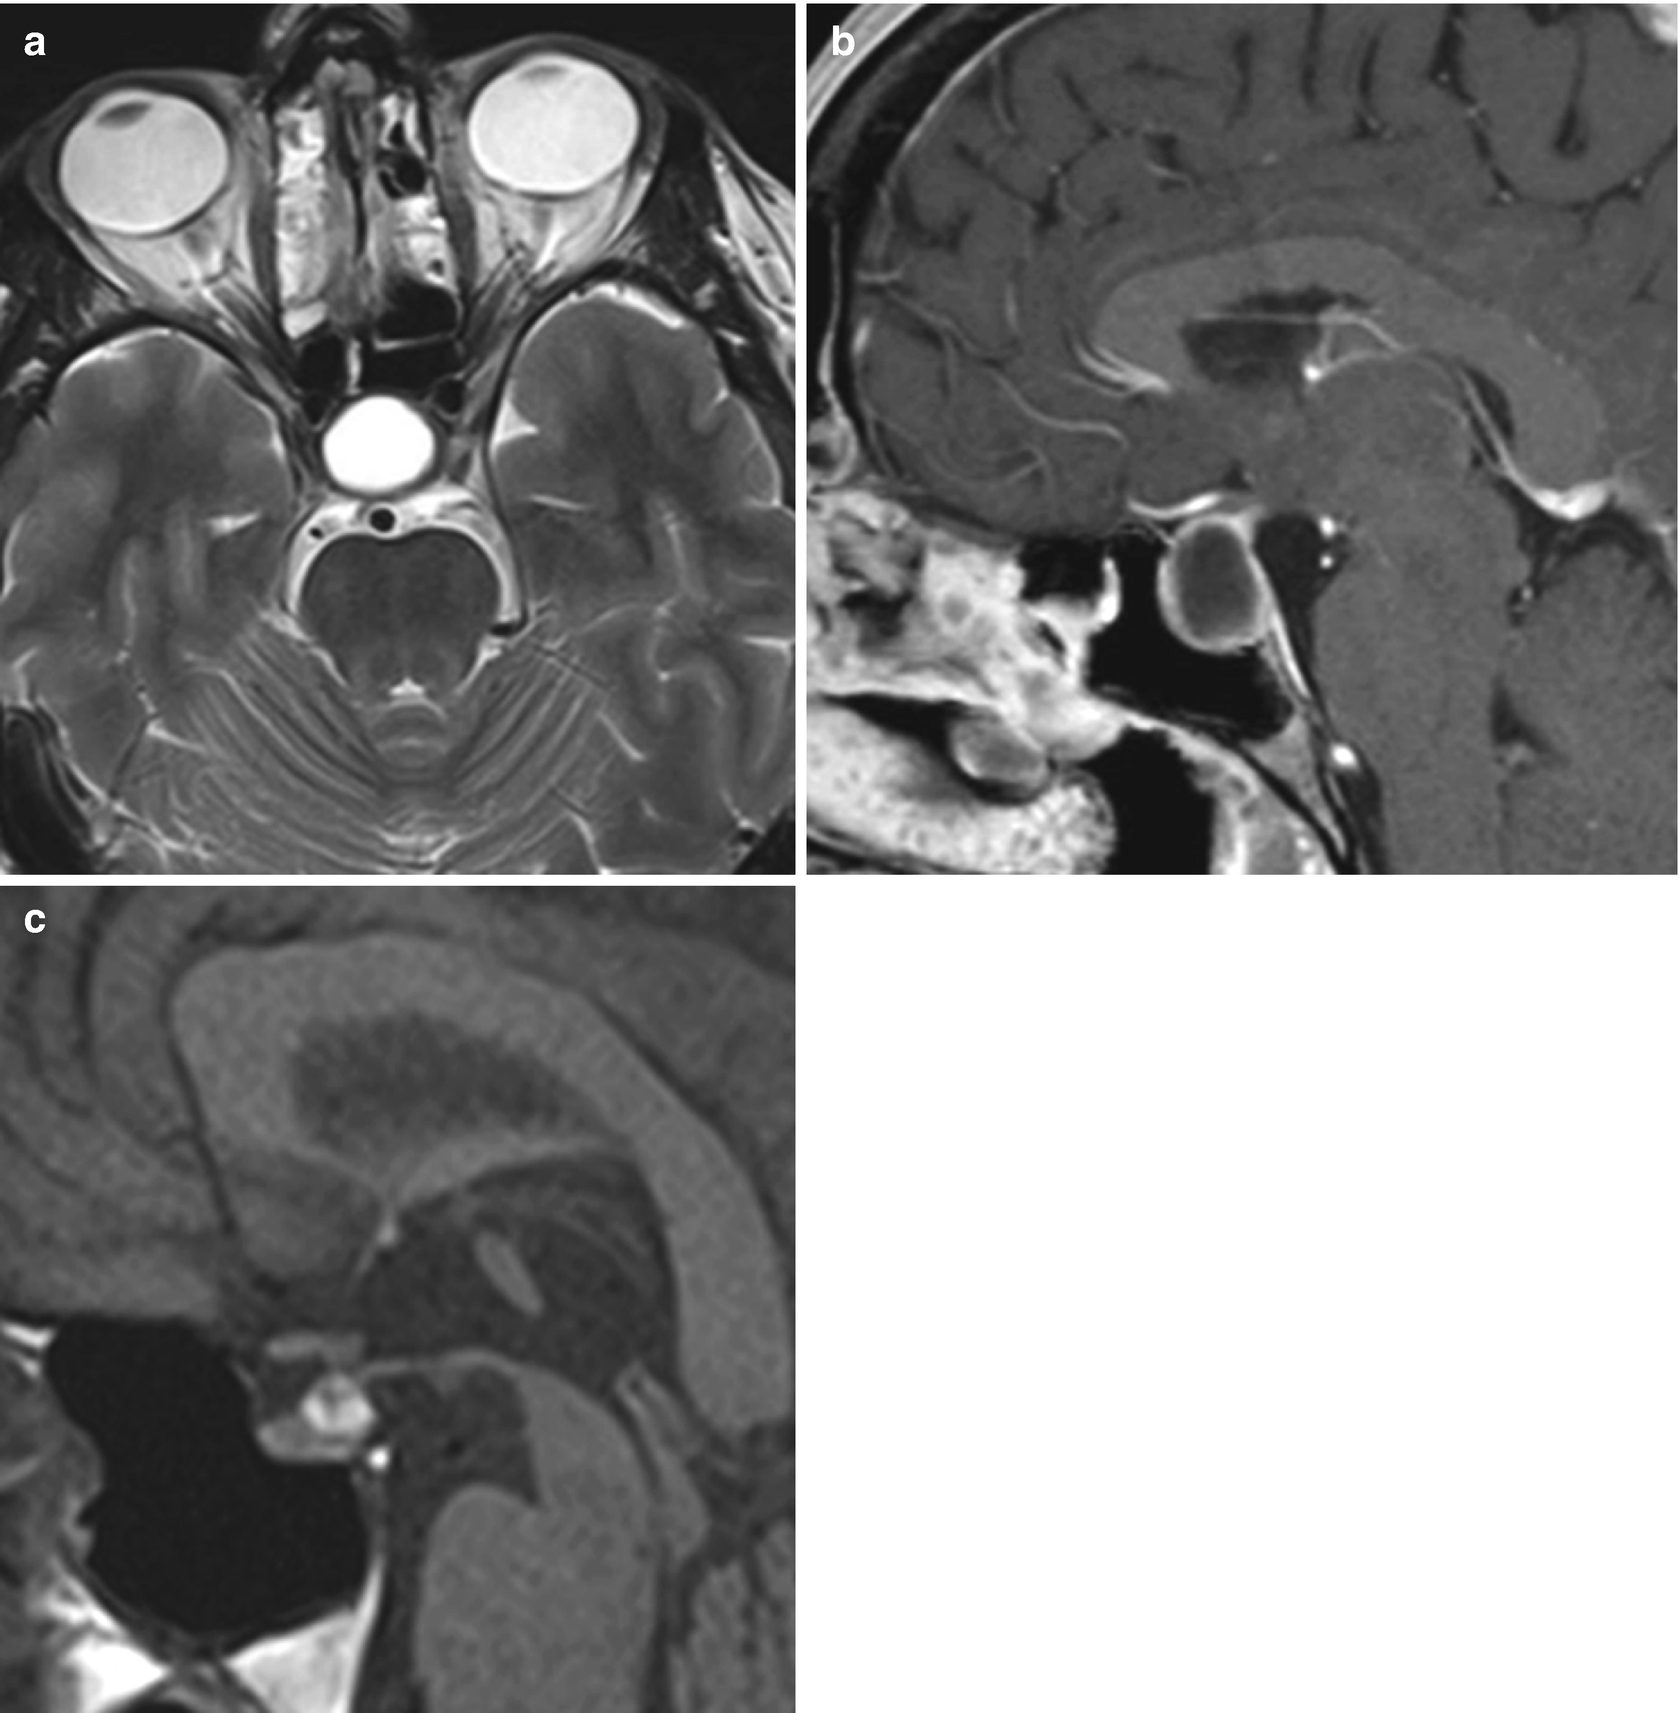

MRI T2-weighted axial image a T1-weighted post-gadolinium axial b and coronal images c demonstrate an extra-axial expansive lesion dotted circles mildly hyperintense with heterogenous contrast enhancement surrounded by cystic components. The presence of a fluid-fluid level a hypointense rim on T2-weighted images septation and an off-midline location were more common with pituitary adenomas whereas the presence of an intracystic nodule was more common with Rathke cleft cysts.

Multiple logistic regression analysis showed that cystic pituitary adenomas and Rathke cleft. MRI is superior in most cases in which differentiation of soft tissues is necessary. A cystic hygroma also known as a cystic lymphangioma is a benign fluid-filled sac caused by a malformation of the lymphatic system. Quantitative parameters of magnetic resonance imaging cannot predict human epidermal growth factor receptor 2 HER2 status in rectal cancer. An MRI is usually completed to assess for tumors and a bone density test will provide information about bone strength and possible disorders eg osteopenia osteoporosis. Differential diagnosis include adenoma myelolipoma cyst lipoma pheochromocytoma adrenal cancer metastatic cancer hyperplasia and tuberculosis.

Differentiation Between Cystic Pituitary Adenomas And Rathke Cleft Cysts A Diagnostic Model Using Mri American Journal Of Neuroradiology